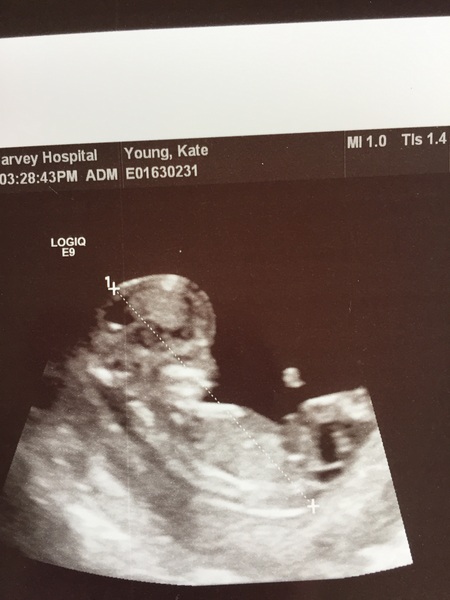

Scan here went really well! So lovely to see baby.

Dates the same.

She looked at nub and thinks girl......but quite early at 11+4 so that might change.

Scan this afternoon. Everything is fine and EDD is 5/4/17 now